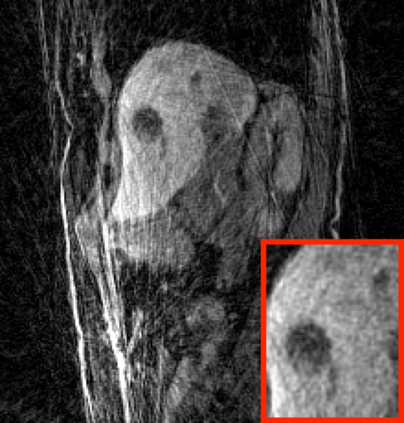

Deep neural networks for medical image reconstruction are traditionally trained using high-quality ground-truth images as training targets. Recent work onNoise2Noise (N2N) has shown the potential of using multiple noisy measurements of the same object as an alternative to having a ground truth. However, existing N2N-based methods cannot exploit information from various motion states, limiting their ability to learn on moving objects. This paper addresses this issue by proposing a novel motion-compensated deep image reconstruction (MoDIR) method that can use information from several unregistered and noisy measurements for training. MoDIR deals with object motion by including a deep registration module jointly trained with the deep reconstruction network without any ground-truth supervision. We validate MoDIR on both simulated and experimentally collected magnetic resonance imaging (MRI) data and show that it significantly improves imaging quality.